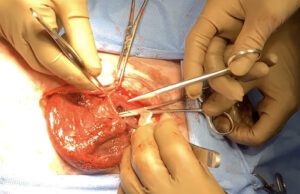

・逆行性に尿道結石を膀胱に戻した

・腹腔内に大量の血様貯留を認めた

・膀胱は赤褐色に変色

・膀胱頚部の不連続部より切開を加え、多数の小石状の結石を摘出

・切開部をトリミング後、吸収糸連続縫合にて閉鎖